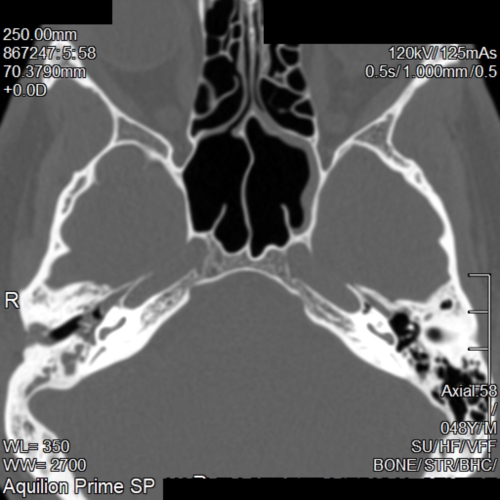

The CT scan report came back saying I had Chronic Otomastoiditus and showed opacification of the Mastoid bone and middle ear space. (See pictures)

I think I can see thickening of the of the right ear drum. But I'm not 100% sure. Maybe any curious radiologists out there can correct me. The right middle ear space is opacified so I find it difficult to see any obvious changes to the ossicular chain.